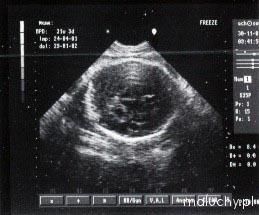

30 tydzień ciąży

ciąża tydzień po tygodniu. Zdjęcie USG - 30 tydzień ciąży